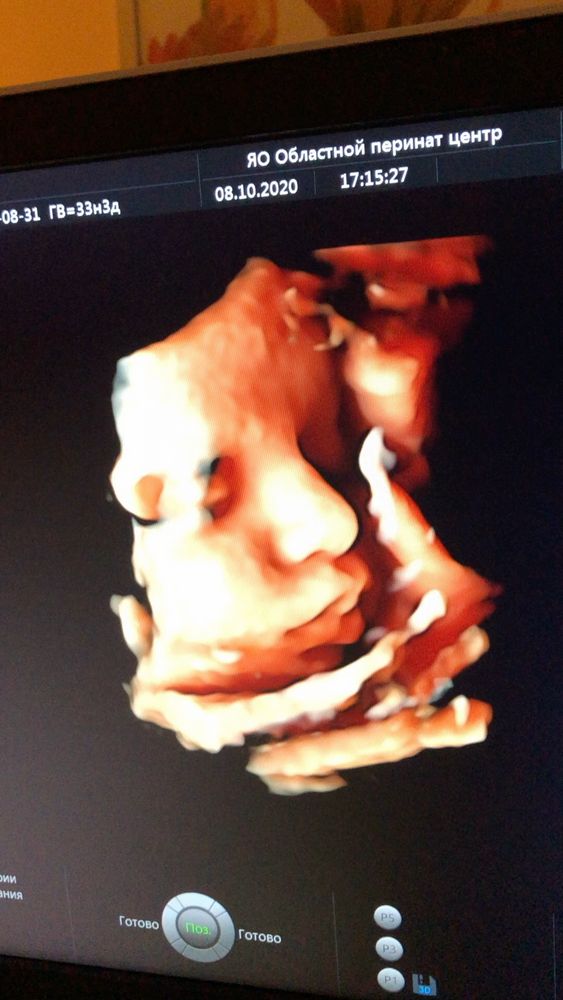

Совсем скоро возьмём его на ручки и увидим,чья это копия)) а пока что сравниваем с узи) Похож на мужа или на меня?)

Совсем скоро возьмём его на ручки и увидим,чья это копия)) а пока что сравниваем с узи) Похож на мужа или на меня?)

Анна Петрова, мне тоже кажется,что никого не обделил,на обоих похож)) губы кстати папины,когда узи делали ,смотрела,у него очень пухлые губки 😍у мужа тоже пухлые) у меня нет,но у мелкого мой бугорочек на верхней губе посередине)